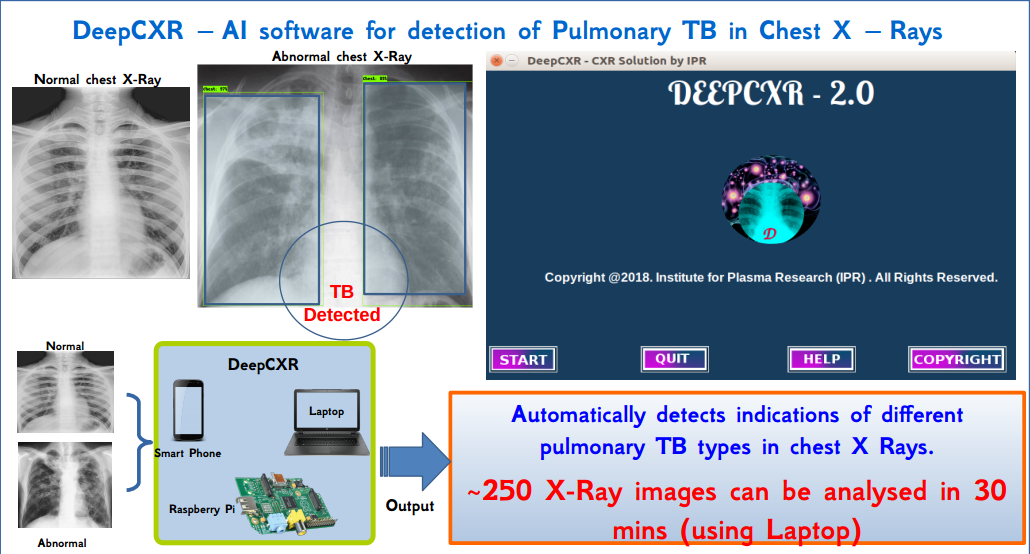

Artificial Intelligence Software for Fast Automated Screening of Chest Ailments (such as TB) using Chest X- Ray Images, in collaboration with ICMR headquarters, Delhi. -https://tb.ai.icmr.org.in/ai4tb/

Other potential areas of AI application like hand movement, gesture recognition, big data analysis are part of other collaborations. DeepCXR

Institute of Plasma Research developed AI tool for detection of TB and other lung disease using Chest X-ray, was tested on limited data set and therefore the entire range of variables have not been covered.

MOU signed & training of tool initiated on the data of culture confirmed X-rays from previous surveys which includes data from four zones of India.

At present tools are in advanced stage of testing with numerous images from various sources. This work is being carried out in collaboration with Civil Hospital, Ahmedabad, ICMR, head quarter Delhi, NIRT, Chennai and other participating institutes/medical colleges in India. The software has the capability of processing more than 250 images in 30 mins.

A central website has been developed at ICMR Delhi https://tb.ai.icmr.org.in/ai4tb/

A pre processing software was developed by IPR and training was given to all participant institutes .

For our software DeepCXR we need digital CXR(chest x-ray). For this purpose a prototype of digitizer of chest X-rays was developed and tested.